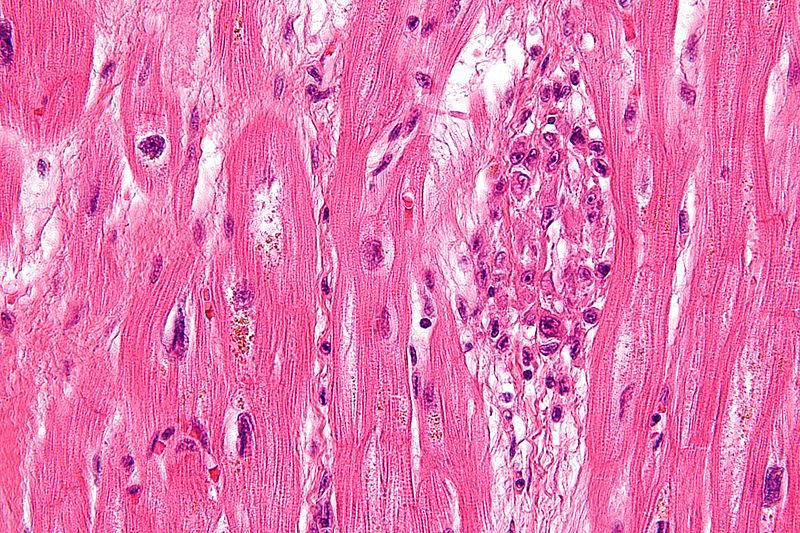

Histology classically shows reactive histiocytes with slender, wavy nuclei are known as Anitschkow cells, Aschoff bodies, gigantic cells, and fibrinoid material.